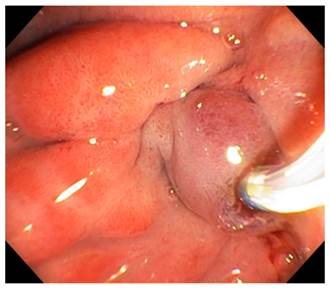

Se procedió a la realización de ultrasonografía biliopancreática con el equipo Pentax lineal y se encontraron cambios sugestivos de pancreatitis crónica y dilatación del colédoco, pero en la fase endoscópica del examen se observó edema y eritema del bulbo y la segunda porción del duodeno con engrosamiento ecográfico de la pared duodenal que rodea la cabeza del páncreas, dependiente de las ecocapas 1 y 2, y parcialmente de la 3; es decir, de la mucosa y la submucosa; pero estaba conservada la ecoestructura de las capas, sin adenopatías perilesionales. La punción no mostró lesiones que sugirieran neoplasia. Se decidió realizar colangiopancreatografía retrógrada endoscópica (CPRE) y se encontró al paso del duodenoscopio un gran edema, eritema y erosión en la segunda porción del duodeno; y las papilas mayor y menor edematizadas con dilatación del colédoco, pero sin cálculos (Figura 1). Se realizó la colocación de stent biliar para asegurar un adecuado drenaje. Por la sospecha de lesión ampular se tomaron biopsias, las cuales fueron reportadas como “proceso inflamatorio sin evidencia de displasia o neoplasia”. La evolución del paciente fue favorable y se mantiene bajo seguimiento clínico periódico, con tratamiento enzimático oral y recomendaciones nutricionales, por lo cual se consideró que el paciente cursó con una pancreatitis del surco que comprometió principalmente el duodeno y las dos papilas, y generó cambios obstructivos biliares y pancreáticos.

La CPRE es un procedimiento técnicamente difícil ya que el posicionamiento del duodenoscopio en presencia del edema del duodeno limita la visualización de la papila. El colédoco distal presenta una estenosis sin compromiso en el conducto pancreático principal. El conducto de Santorini presenta obstrucción por tapones de moco o simplemente por el gran edema perilesional 4,32. En nuestro paciente, los hallazgos endoscópicos mostraron un importante edema del duodeno y la región peripapilar (Figura 3).